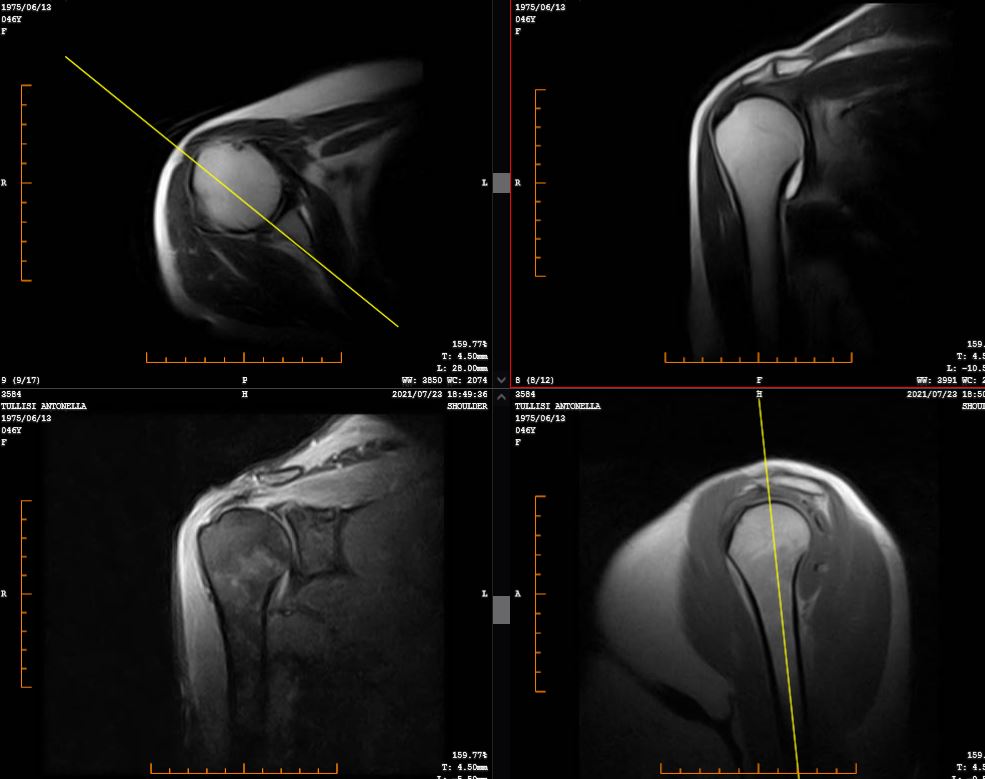

Il referto riporta: “rottura completa del tendine del sovraspinato con completa atrofia del ventre muscolare – quadro compatibile con lesione inveterata.”

Un elemento del referto merita particolare attenzione: l’atrofia completa del ventre muscolare. Questo dato indica chiaramente che la lesione non è recente, ma presente da tempo.

Eppure il paziente, fino a poche settimane prima, non riferiva dolore significativo e svolgeva regolarmente attività fisica.

Il quadro complessivo era molto più coerente con una microinstabilità funzionale con deficit di controllo neuromuscolare che con una lesione tendinea acuta sintomatica.

In altre parole, la risonanza descriveva la struttura, mentre il problema clinico era la gestione del movimento e del carico.

La rottura del sovraspinato, ovviamente, è rimasta. Ma non era quella la causa principale dei sintomi.

Quella era una descrizione anatomica. La diagnosi funzionale corretta era: “microinstabilità di spalla su quadro degenerativo cronico, con deficit di controllo e sovraccarico reattivo.”